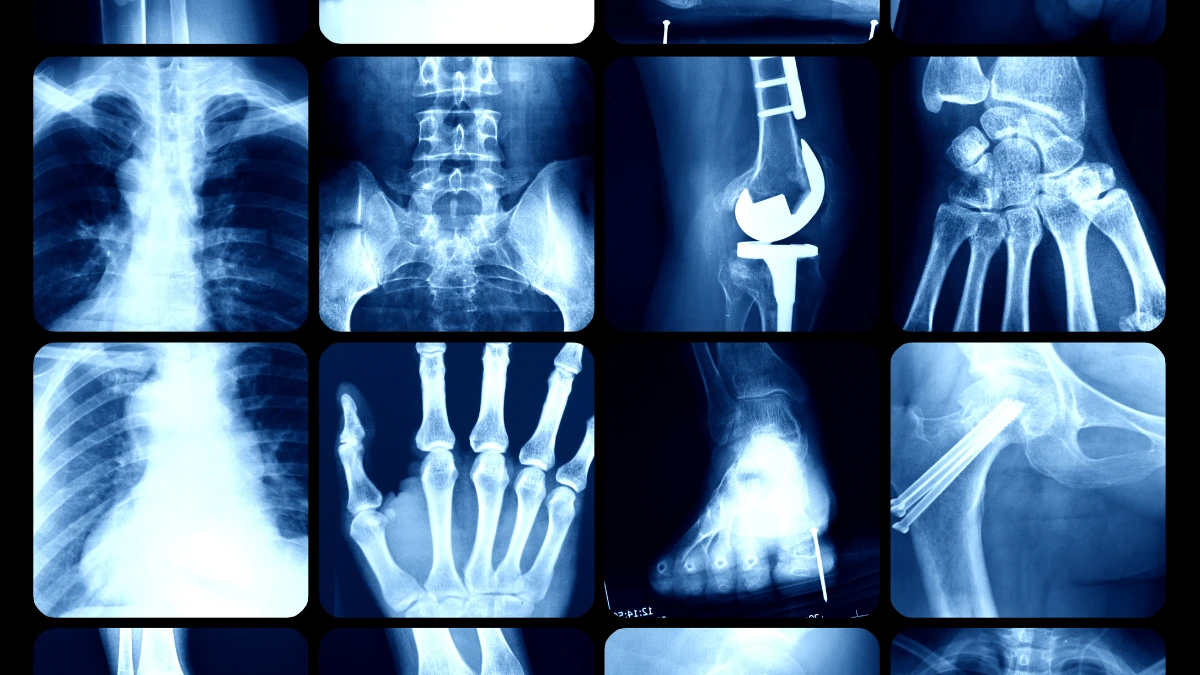

From the many benefits provided by X-ray detectors, this tool is used by many sectors, one of which is the medical industry. X-ray detector for medical industry are used to capture and measure X-ray radiation passing through the patient’s body to produce images.

X-ray detector for medical industry is used to capture and measure X-ray radiation passing through the patient’s body to produce images.

This device can visualize the internal body without the need for surgery, thus greatly assisting doctors in diagnosing and planning treatment.

In the medical world, this detector is applied in various needs for radiography, fluoroscopy, and CT scans.

- Radiography: Used to capture images of organs and tissues in the body, such as bones, lungs, and heart.

- Fluoroscopy: Used to produce moving images in real time to monitor the movement of organs or contrast agents in the body.

- CT scan: Used to produce cross-sectional images of the body through rotating X-ray scans.